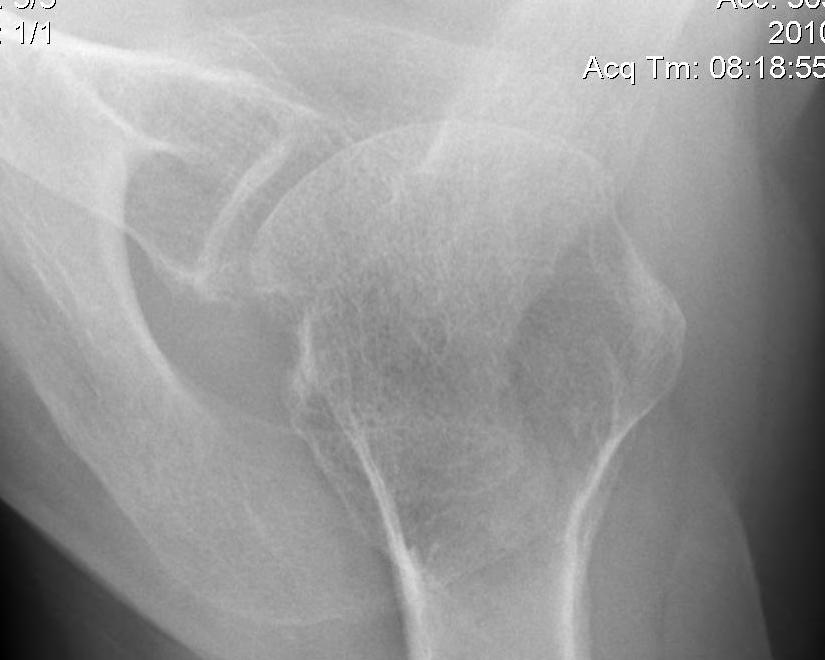

Bony bankart / glenoid rim fractures

Acute bony bankart / glenoid rim fractures

- ? acute repair to reduce instabilty

- ? avoid Latarjet procedure later

Results

- systematic review of arthroscopic bony bankart repair

- 21 studies with 769 patients

- recurrent instability 12%

- return to sport 91%